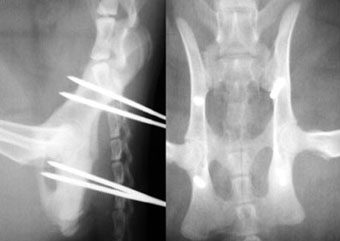

他院からの依頼症例

体重3kg、5歳齢の猫。

腸骨体と恥骨骨折および仙腸関節離断をおこしていました。

写真上段: 手術前

写真中段: 手術後

6本の創外固定ピンを刺入して骨盤構造を支えています。

写真下段: ピン抜去後

骨盤構造は正常に近い状態に回復しています。 |